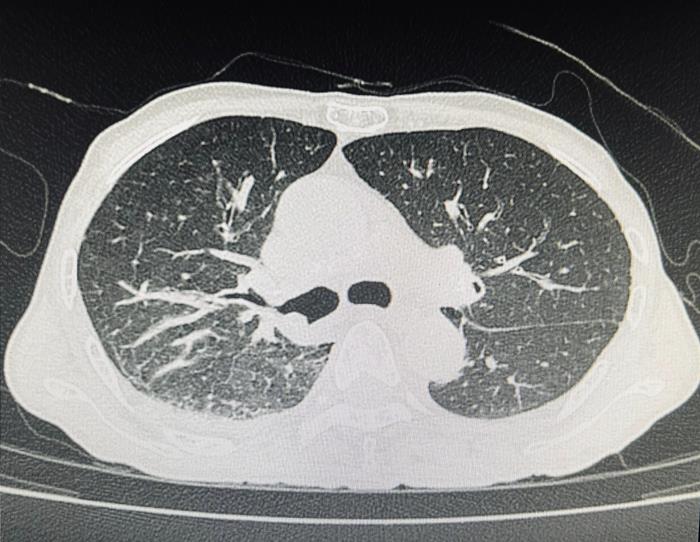

ผู้ป่วยรายนี้เป็นเพศชาย วัย 70 ปี มาด้วยอาการไอเรื้อรัง มีเสมหะปนเลือด หอบเหนื่อยจนเดินไม่ค่อยไหว ผอมจนน้ำหนักลด เมื่อเอกซเรย์ตรวจดู พบว่า มีลักษณะคล้ายปอดอักเสบที่ด้านขวาล่างหรือมีอะไรที่คล้ายก้อนมะเร็งอยู่ตรงนั้น

เกิดปอดแฟบอย่างที่เห็นในฟิล์มที่คล้ายลักษณะก้อน ๆ